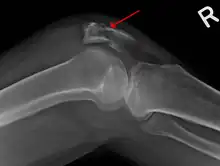

Osteochondral fracture of patella